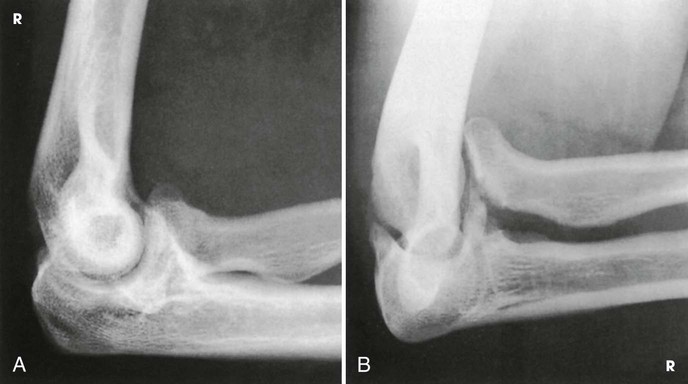

Structures shown

The resulting projections show an open elbow joint between the radial head and capitulum (Fig. 4-142) or between the coronoid process and trochlea (Fig. 4-143) with the area of interest in profile. These projections are used to show pathologic processes or trauma in the area of the radial head and coronoid process. The value of the projections is evident in the trauma images shown in Fig. 4-144.1